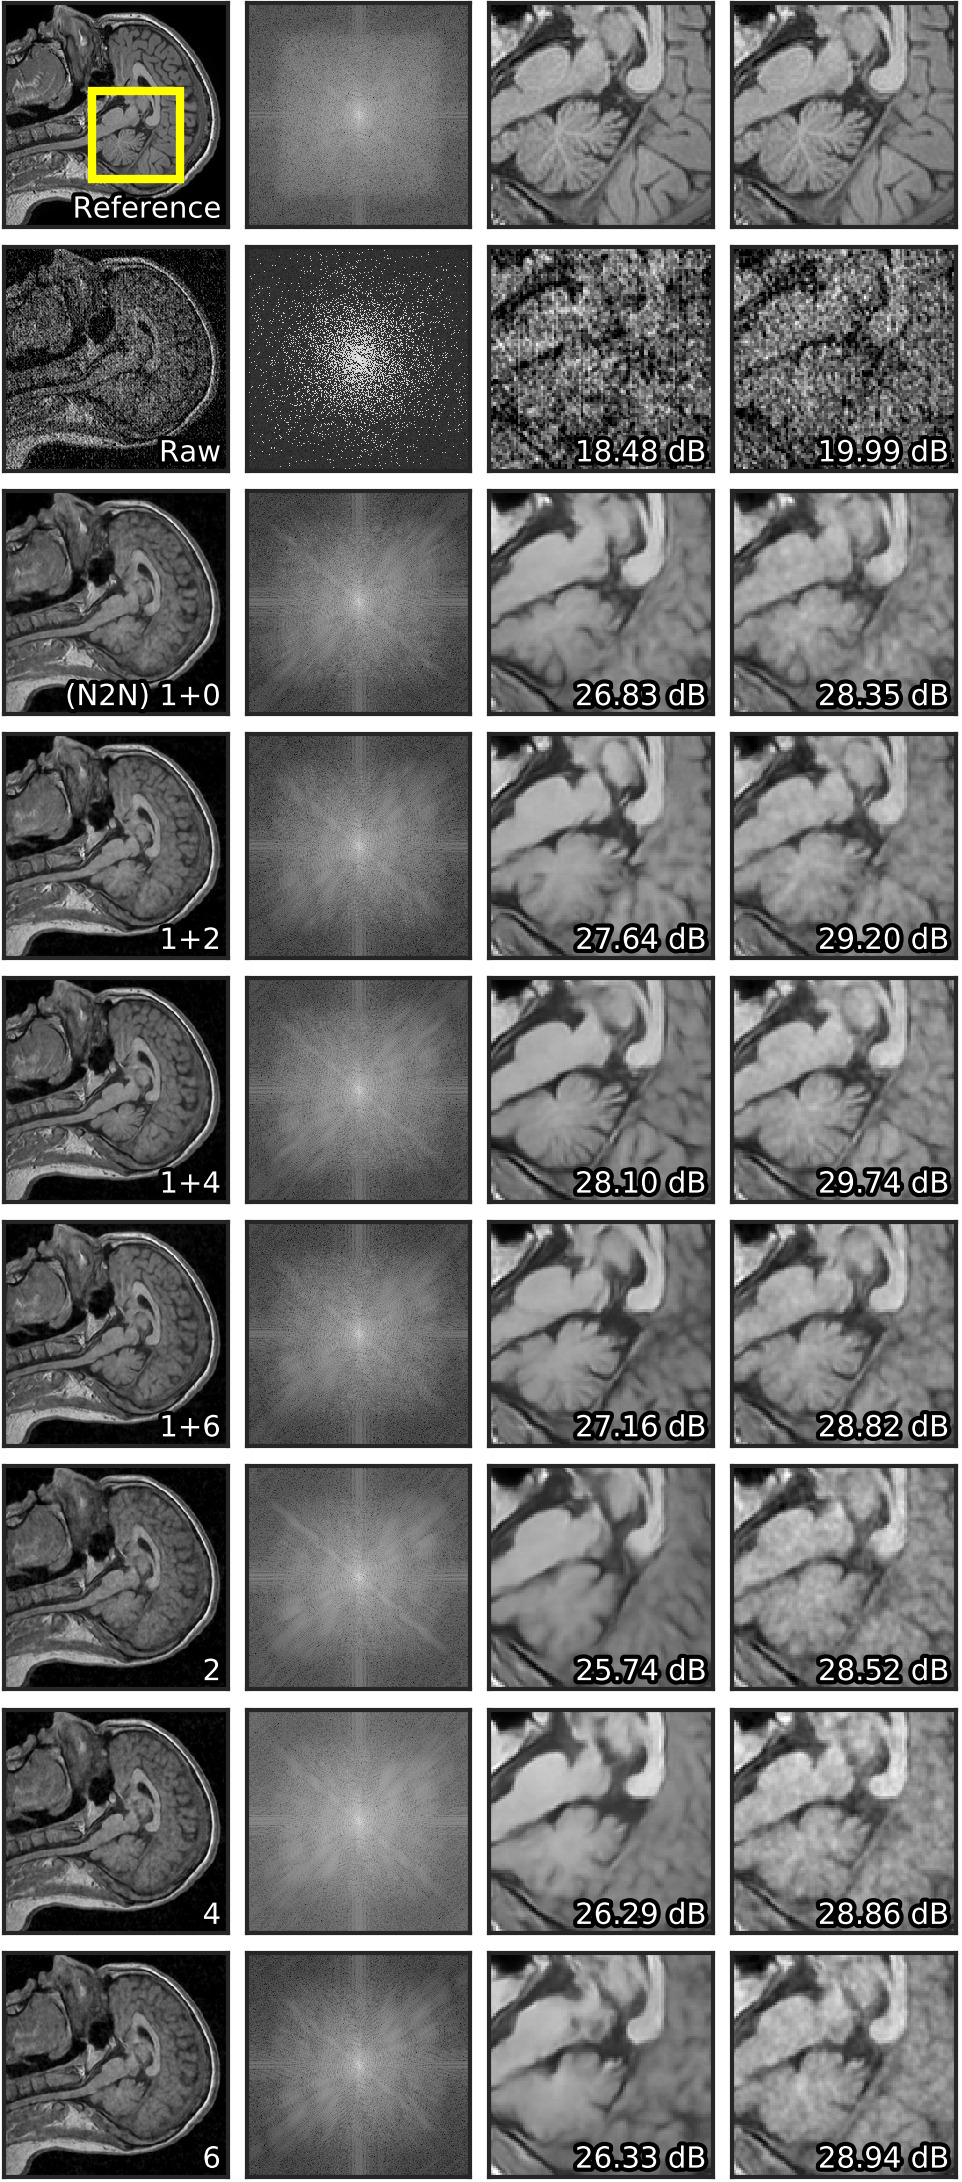

Adding four neighbors to the Noise2Noise input increased PSNR by dB both before and after post-processing (Table 1). Overall, limiting the number of neighbouring planes to four (two from each side) proved optimal, resulting in the greatest performance benefits with reasonable computational costs in both modes (Figure 4). Using a single image stack for training in a self-supervised mode with four neighbours in the input, we outperform the original Noise2Noise model by dB.

Visually, the level of detail in MRI denoised with Noise2Stack in copy-supervised mode has noticeably increased comparing to Noise2Noise, as can be seen in Figure 3 (additional illustrations provided in Supplementary material, Figure S1). Brain gyri in the reconstructed images are clean and sharp even for the cerebellum where they are tiny. In self-supervised mode Noise2Stack results are expectedly less detailed and match Noise2Noise by sight. However, this mode demands twice less data, being able to learn from a single copy. For the fluorescent microscopy, Noise2Stack in self-supervised mode did not outperform supervised Noise2Clean, but has shown comparable results.

| a) Image | b) Spectrum | c) Crop | d) Crop (PP) |